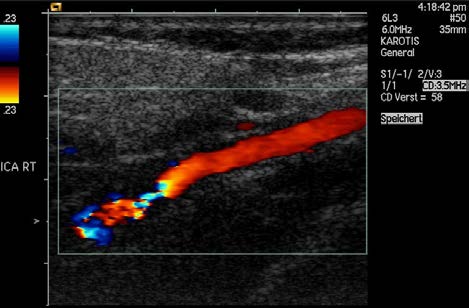

Another major use of ultrasound in medical diagnostics is to detect motion and determine velocity through the Doppler shift of an echo, known as

Doppler-shifted ultrasound. This technique is used to monitor fetal heartbeat, measure blood velocity, and detect occlusions in blood vessels, for

example. (See Figure 17.47.) The magnitude of the Doppler shift in an echo is directly proportional to the velocity of whatever reflects the sound.

index-620_1.jpg

index-620_2.jpg

618 CHAPTER 17 | PHYSICS OF HEARING

Because an echo is involved, there is actually a double shift. The first occurs because the reflector (say a fetal heart) is a moving observer and

receives a Doppler-shifted frequency. The reflector then acts as a moving source, producing a second Doppler shift.

Figure 17.47 This Doppler-shifted ultrasonic image of a partially occluded artery uses color to indicate velocity. The highest velocities are in red, while the lowest are blue. The blood must move faster through the constriction to carry the same flow. (credit: Arning C, Grzyska U, Wikimedia Commons)